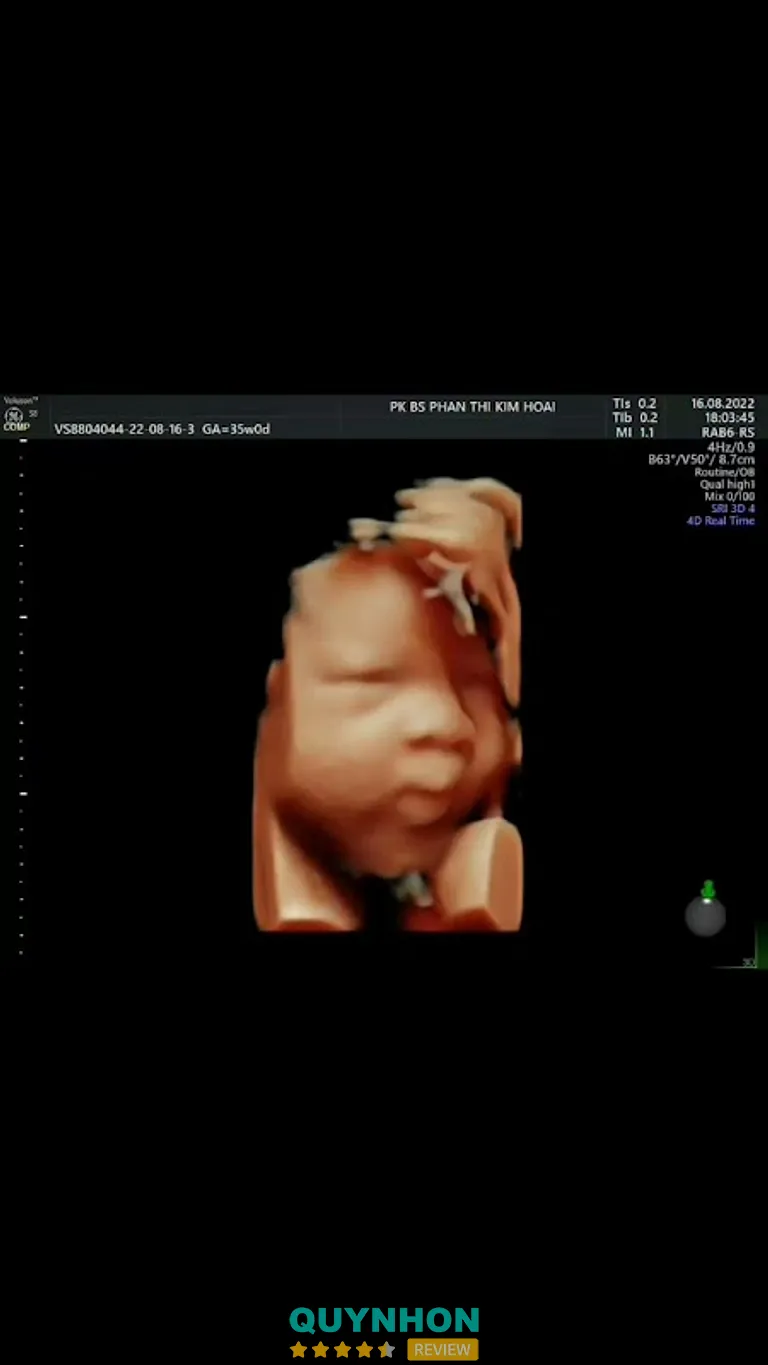

Siêu âm sản khoa – siêu âm chẩn đoán hiện đại

Phòng khám được trang bị máy siêu âm GE Voluson, dòng máy cao cấp trong lĩnh vực sản phụ khoa, hỗ trợ:

Nhờ hệ thống máy móc hiện đại, hình ảnh siêu âm rõ nét, hỗ trợ tốt cho việc theo dõi thai kỳ, phát hiện sớm các bất thường và đánh giá chính xác tình trạng sức khỏe mẹ và bé.